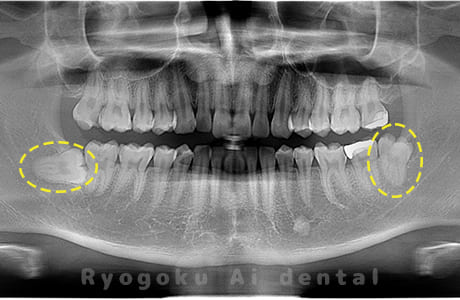

Case01

-

- 原因

- 水平埋伏智歯

- 治療内容

- 下顎の水平埋伏智歯を抜歯

<リスク・副作用>

手術後は痛み、腫れ、痺れなどの副作用が生じる場合があります。